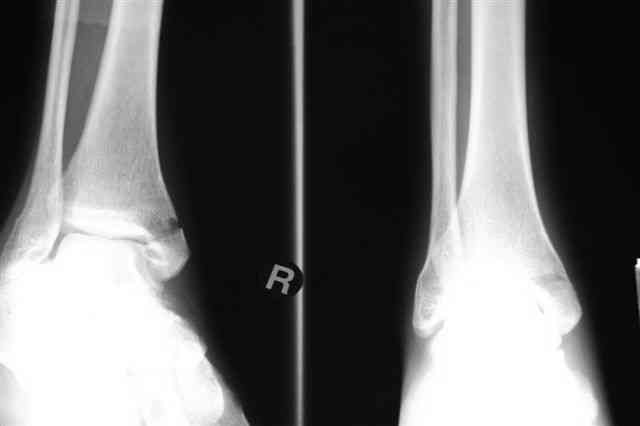

Лодыжку так ипрооперировал двумя 3.5 мм шурупами пришлось открыть - закрыто не удалось адекватно отрепонировать, при открытии - надкостничная

интерпозиция.

Бедро фиксировал длинной DCS.

По типу бриджинг плэйтин, крюком удалось низвести малый вертел и фиксировать винтом для восстановления медиальной стенки.

Снимки бедра и голеностопа еще не сфотографировал, обязательно представлю на форум

В приложении отправляю послеопер. снимки бедра и лодыжки обсуждаемого вчера больного.